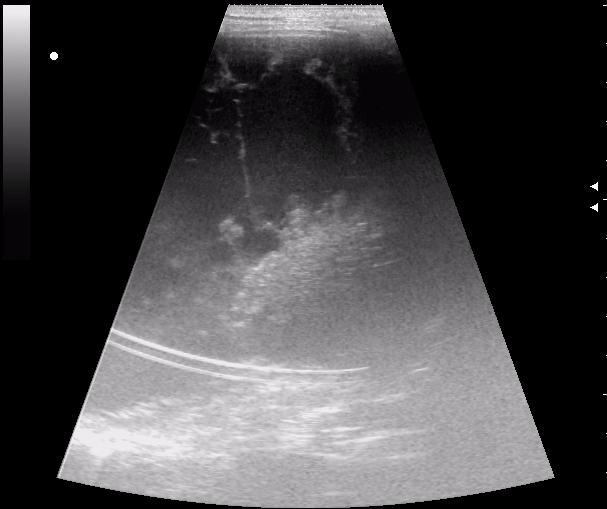

5-летний ребенок, поступил в клинику через 40 мин после случившегося ДТП ( отец не справился с управлением, машина - в хлам, восстановлению не подлежит)

на фоне выраженной диффузной неоднородности паренхимы - нарушение целостности капсулы (09.02.2010. 8.13)

наличие гиперэхогенных усастков без четких контуров позволяет поставить диагноз - разрыв печени

селезенка - ишемическая.

подкапсульная гематома